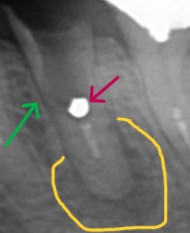

【ポスト底部に取れなかったメタルコアーと根尖に病巣、近心の根管壁が異常に薄い】

【赤矢印 取り切れていないメタルコア―】

【黄色囲み部分 根尖病巣】

【緑色矢印 異常に薄い根管壁】

診断 ガッタパーチャポイントが根尖付近まで到達していないことから感染を起こしている。近心の異常に薄い根管壁はメタルコアーを除去する際にパーフォレーションを起こしている可能性がある。通法通り治療すれば治癒する。ただし歯肉縁下まで歯質が失われているので、根管治療が落ち着いたら臨床的歯冠延長手術は必要。